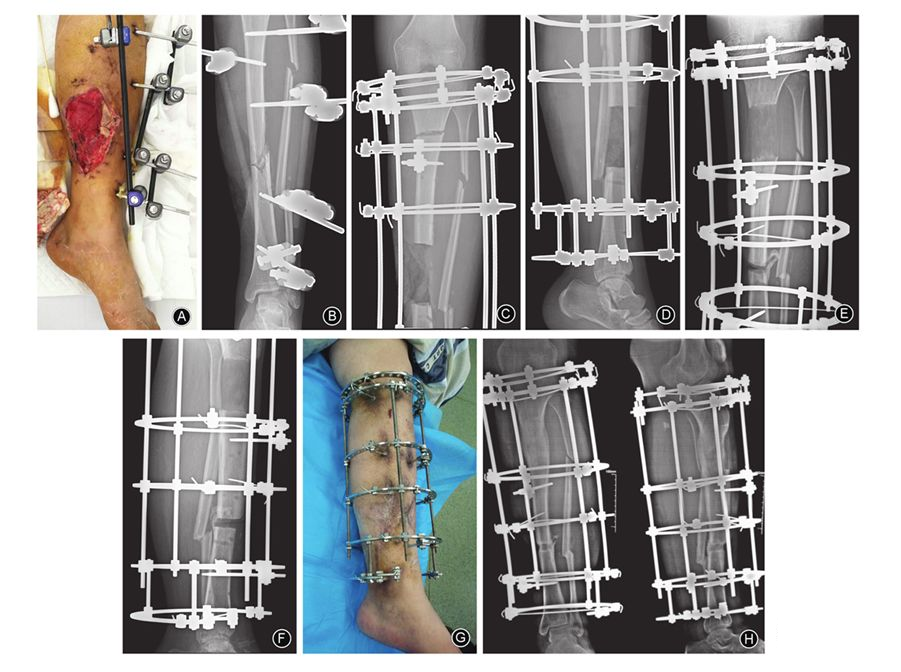

图2 男,22岁,车祸伤致左小腿开放性骨折 A 外固定架固定术后1个月,大体照片示左小腿中段内侧9 cm×8 cm皮肤缺损区,伴感染死骨形成 B 术前正位X线片示左胫骨无愈合征象 C,D 骨搬移术后1周,左胫骨正、侧位X线片示骨缺损约10 cm E,F 骨搬移术后4个月,正、侧位X线片示延长骨段矿化良好,断端对合,下肢力线无明显偏移 G 小腿内侧创面给予开放换药,骨搬移术后4个月大体照片示创面完全愈合 H 骨搬移术后9个月,正侧位X线片示骨搬移断端对合良好